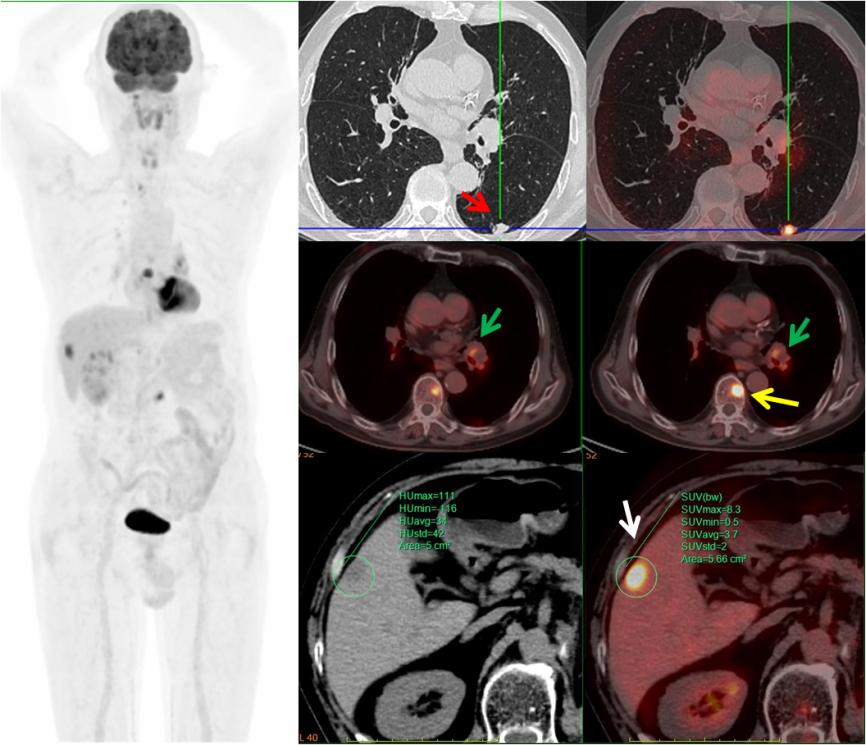

病例3,中年男性,左腎癌術(shù)后三個月,PET/CT示左肺下葉(紅箭)、左肺門淋巴結(jié)(綠箭)、肝臟(白箭)、多發(fā)椎體(黃箭)高代謝灶,考慮左肺下葉原發(fā)MT可能,病理證實為小細胞神經(jīng)內(nèi)分泌癌。